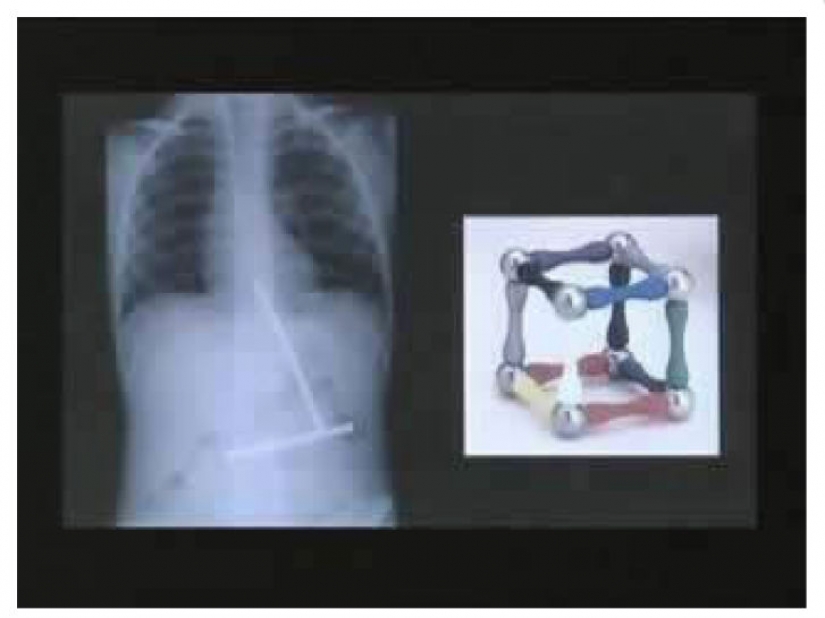

One little boy ate one piece toy with magnet at a time. When finally all of the toys were in the stomach of the boy, they came together.